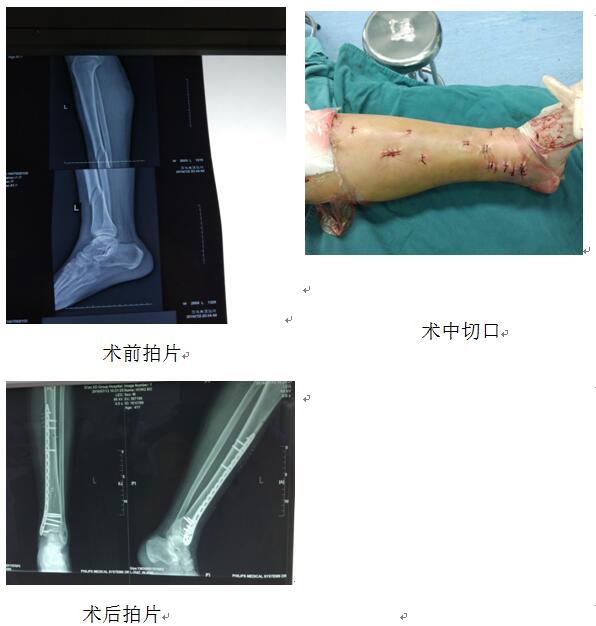

洪×,男,41歲,于2016年7月2日以“車禍致左小腿疼痛、出血、活動受限2小時余”收住我科。入院診斷:1、左脛骨粉碎骨折2、左小腿挫裂傷3、右足背裂傷并趾伸肌腱斷裂4、右足踇趾近節(jié)骨折。入院時左下肢??撇轶w:左小腿腫脹明顯,小腿中下1/3處成角畸形。小腿上段脛前有一約6cm長斜行裂傷,深達(dá)骨質(zhì),創(chuàng)面軟組織挫傷重,傷口污染明顯。入院后我科值班醫(yī)生行開放傷清創(chuàng)縫合、肌腱探查吻合術(shù),術(shù)后患肢支具制動及對癥治療。根據(jù)傳統(tǒng)治療方案,至少傷后半月皮膚條件明顯改善才可行骨折切開復(fù)位內(nèi)固定手術(shù)治療,且因錯過骨折治療的最佳時機(jī),并且術(shù)中長切口、廣泛剝離骨膜也為以后骨折的愈合留下了隱患。在我科張富軍主任的帶領(lǐng)下,于患者傷后第10天我科即開展MIPPO技術(shù)為患者施行經(jīng)皮微創(chuàng)左脛骨骨折閉合復(fù)位鋼板內(nèi)固定術(shù)。術(shù)中閉合復(fù)位骨折后僅在左小腿遠(yuǎn)近端行2-3cm小切口經(jīng)骨膜上插入鋼板,皮膚刺孔上螺釘固定骨折。手術(shù)時長約1小時,獲得治療最佳效果。以下就是患者術(shù)前、術(shù)后拍片及切口情況圖片。此類手術(shù)的開展也標(biāo)志著我科在MIPPO技術(shù)方面達(dá)到了國內(nèi)先進(jìn)水平。